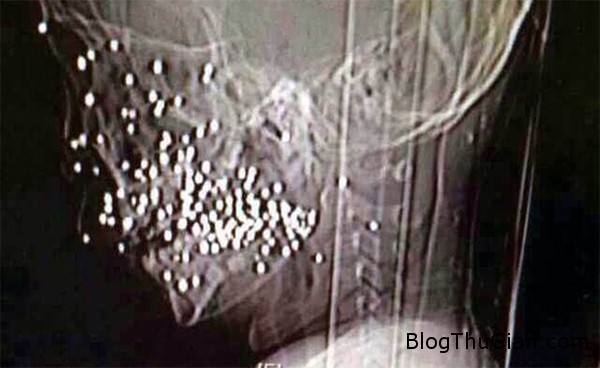

Hình chụp X-quang khuôn mặt bị đạn găm vào của cậu bé.

Ngày 20/8 vừa qua, các bác sĩ Bệnh viện Nhân dân số 9 Thượng Hải không khỏi giật mình khi tiếp nhận ca tai nạn khủng khiếp của một bé trai 8 tuổi, xin giấu danh tính, người tỉnh An Huy, Trung Quốc sau bị gần trăm viên đạn găm vào mặt. Tuy nhiên, rất may mắn là sau ca phẫu thuật kéo dài 5 tiếng đồng hồ, đội ngũ bác sĩ đã gắp bỏ được toàn bộ số đạn ra khỏi cơ thể cậu bé.

Tại đây, các bác sĩ đã gắp bỏ tổng cộng 86 viên đạn găm ở mặt cậu bé và phẫu thuật chỉnh sửa lại xương ổ răng bị vỡ. Hiện cậu bé đang trong quá trình ổn định nhưng vẫn cần phải tiếp tục điều trị trong thời gian sắp tới.